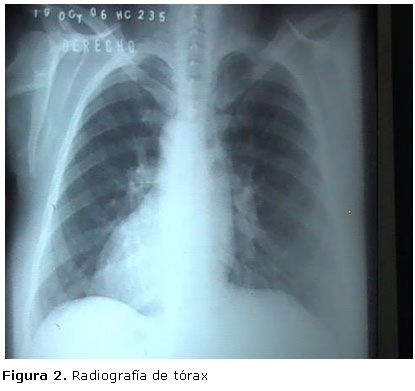

Rayos x de tórax: Corazón a la derecha de la línea media con ápex dirigido a la derecha (Figura 2).

La levocardia es la posición normal del corazón, la dextrocardia es cuando la punta del corazón apunta a la derecha. Si la dextrocardia no se asocia a situs inversus por lo general se acompaña de severas malformaciones cardiacas. La levocardia con presencia de situs inversus también se asocia a múltiples y complejas malformaciones cardiacas 1. En el caso que se muestra, no hay dudas de que se trata de dextrocardia que acompaña a situs inversus totalis, tanto clínicamente como imagenológicamente (Figura 2).

Para corroborar el diagnóstico se realizaron estudios electrocardiográficos (Figura 1) e imagenológicos: ultrasonido, Rx estómago y duodeno (Figura 3 y 4) y Rx tórax (Figura 2).